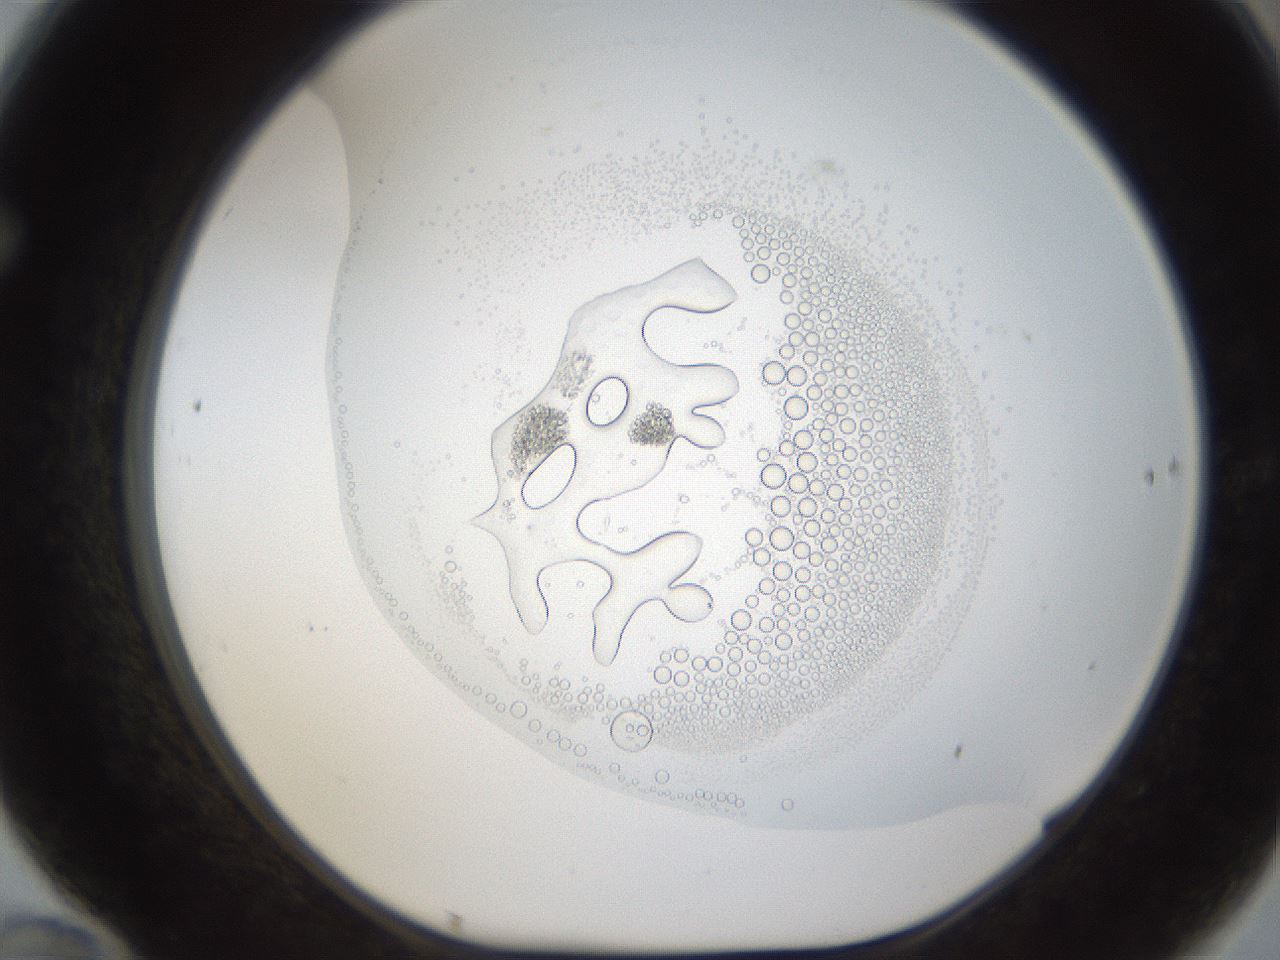

folderID214_plateID1214_batchID3712_wellNum70_profileID1_d1_r69674_ef.jpg